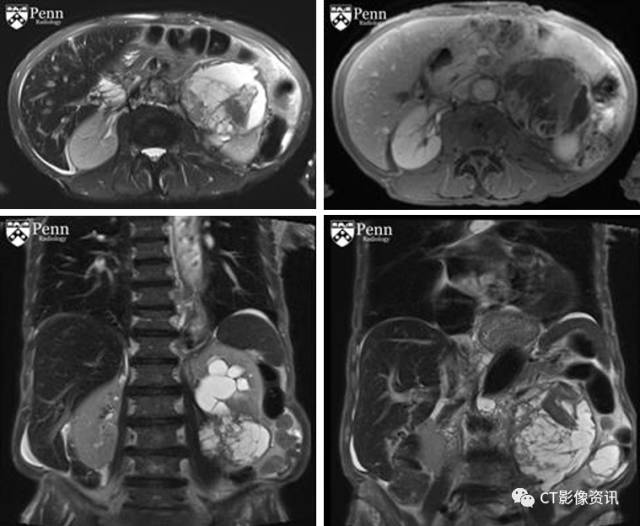

形象学特点: 主要特点:腹膜后巨大肿块,确诊时通常10cm或大于10cm;影像学缺乏特异性,随肿瘤成分的不同影像学表现有较大的差,可以有较大的囊性坏死成分,脂肪和钙化少见。 CT:可见巨大腹膜后肿块,伴囊性和(或)坏死密度;增强扫描呈不均匀强化。 MRI:T1-加权:等到低信号;T2-加权:由于囊性或坏死成分呈等到高信号;增强扫描:不均匀强化。